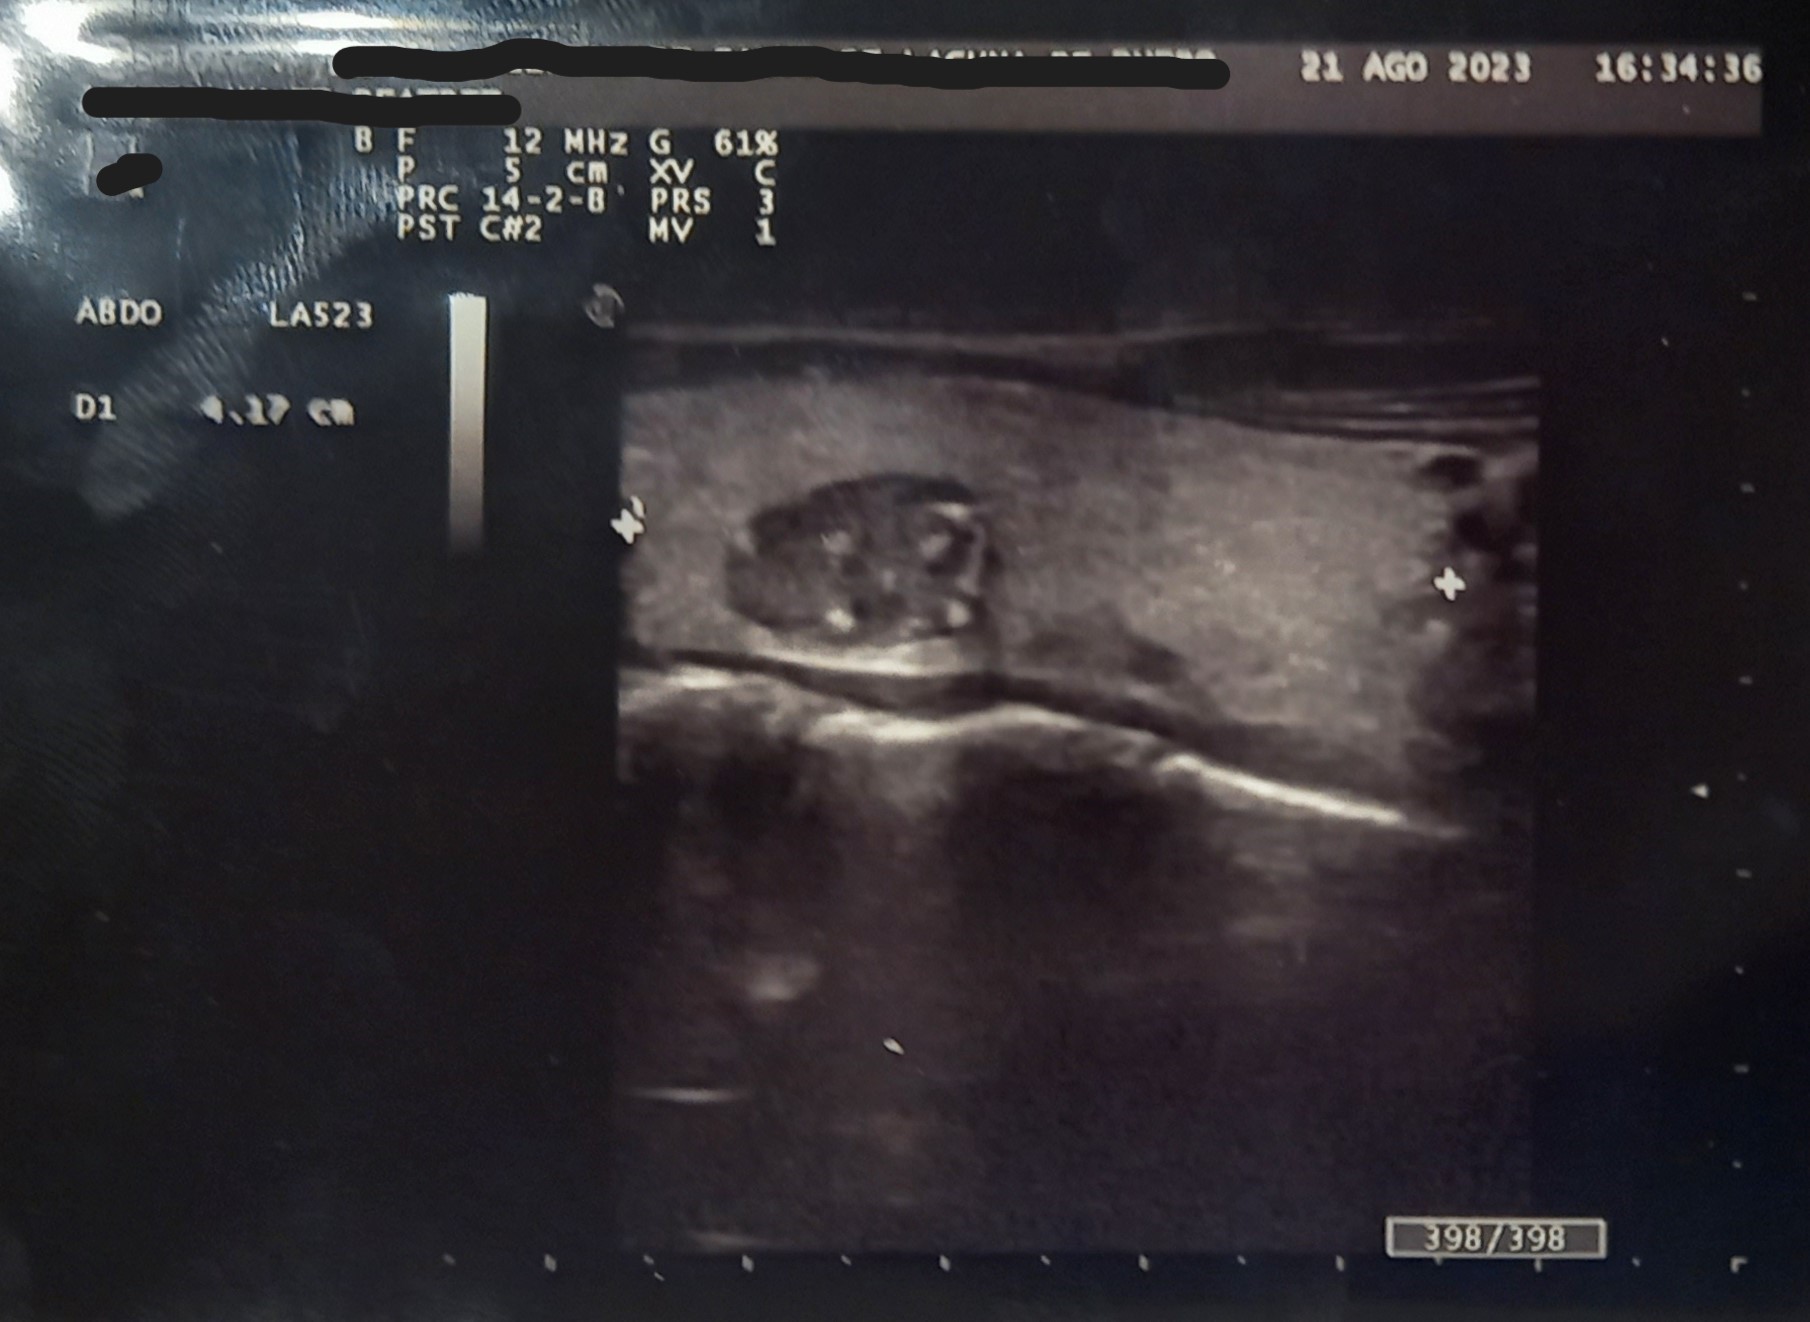

Ecografía en consulta de Atención Primaria. Se observa quiste completo en lóbulo tiroideo derecho, No condiciona aumento importante de tamaño de lóbulo: Dimensiones 14*22*41 mm. Zonas con hiperecogenicidad difusa. Nódulo de características complejas. Ecogenecidad heterogénea zonas anecoicas/hipoecoicas y calcificaciones múltiples. Escala TIRADS: 3.